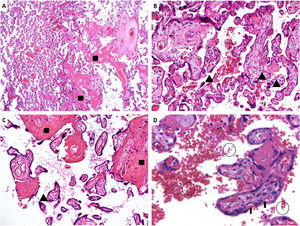

Placental pathology was available in 15 cases (8 Hb SS and 7 Hb SC), with abnormal findings in ten (5 Hb SS and 5 Hb SC). From the 10 placentas with abnormal findings, five placentas were hypoplastic (defined as weight below the 10th centile for gestational age), two of them severely affected (below the 3rd centile), nine showed microscopic features of maternal vascular malperfusion (MVM), formerly known as utero-placental hypoxia. MVM can be divided in two ways: global/partial and segmental/complete.23 Half of the placentas showed global/partial MVM, with small or short hypermature villi for gestational age, accompanied by an increase in syncytial knots, characterizing accelerated villous maturation. Moreover, four placentas presented infarctions, characterizing segmental/complete MVM. Two of the nine placentas showed both patterns of MVM. Extensive infarcts were considered the cause of stillbirths that occurred in two Hb SC patients. Only one patient showed decidual arteriopathy. Five placentas showed accentuated perivillous fibrin deposition (1 Hb SS and 4 Hb SC), and ten cases had sickled erythrocytes in the intervillous space (7 Hb SS and 3 Hb SC). Figure 2 shows representative images of the placental findings.

Sample images of placental histopathology in sickle cell disease patients. A. A panoramic view of a pre-term sickle cell disease placenta with mature term villi. HE: 25x. B. Hypermature villi with syncytial knots. HE: 100x. C. Hypermature villi, with increased syncytial knots and accentuated inter- and perivillous fibrin deposition. HE: 100x. D. Many sickled red blood cells within the intervillous space (circles); normal fetal red blood cells in the villous vessels (arrow). HE: 400x. Rectangles (increased fibrinoid deposition), arrowheads (syncytial knots), sickled red blood cells (circles), fetal red blood cells (arrows). (For interpretation of the references to color in this figure legend, the reader is referred to the web version of this article.)